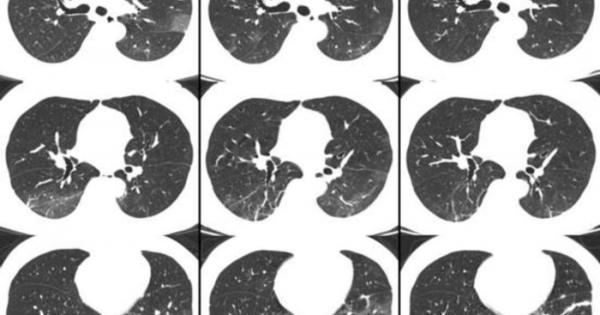

Това което стана известно като Covid 19 или новия коронавирус започна

...... намалявайки способността на организма да поеме кислород и да се освободи от въглеродния двуокис. “Това е обичайната причина за смърт с тежка пневмония”, казва той.

Хората които се възстановяват след заразяване с новия коронавирус могат

...... Световната здравна организация Тедрос Адханом Гебрейес. Най-често съобщаваните симптоми включват треска, суха кашлица и задух, а 80% от пациенти ще премат леко болестта, според СЗО.